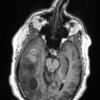

NEOPLASMS (GLIAL)

Glioblastoma, adenoid pattern (9)